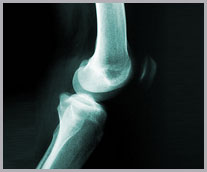

X-rays

X-rays are a type of radiation that uses energy beams for imaging and therapy. How? Electromagnetic rays of short wavelengths can penetrate opaque matter to light rays, and impinge and penetrate substances to affect a photographic plate. This photograph taken with X-rays is commonly practiced in radiography, radiology, radiotherapy and research.